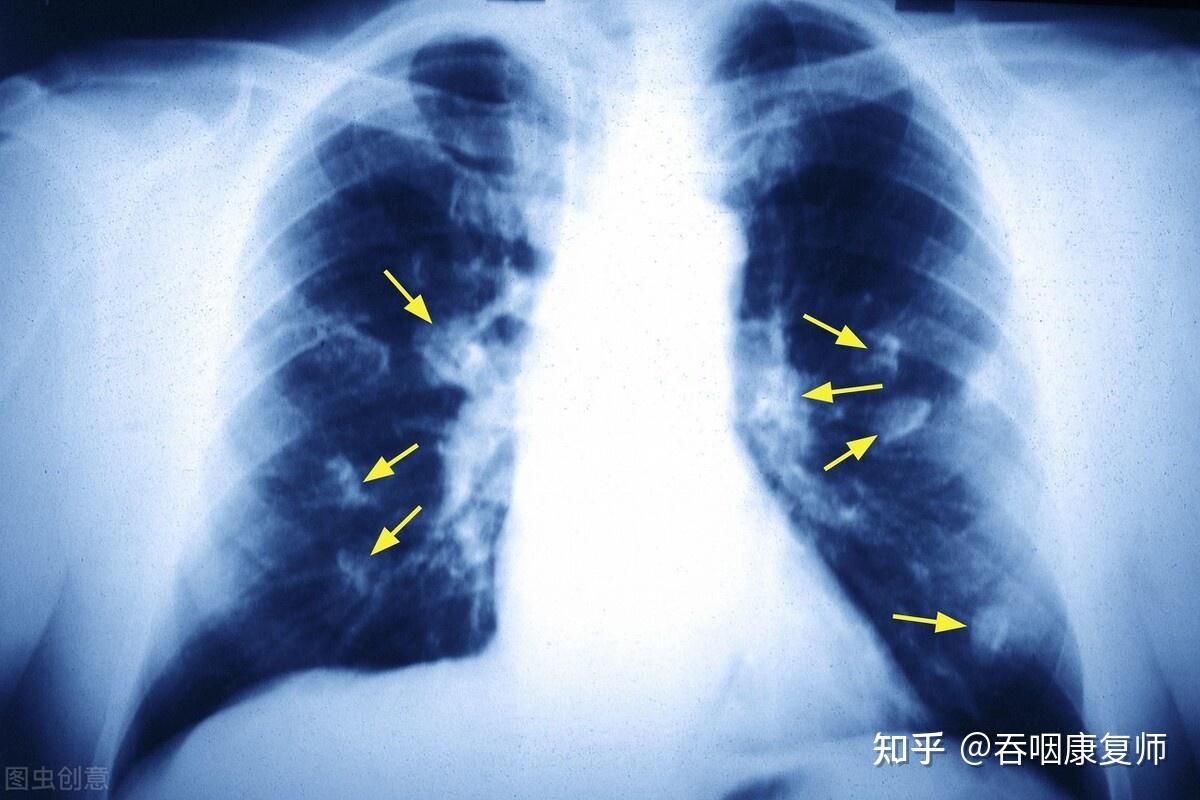

3个信号绝非感冒气管炎看医生怎么说

图片尺寸1200x800